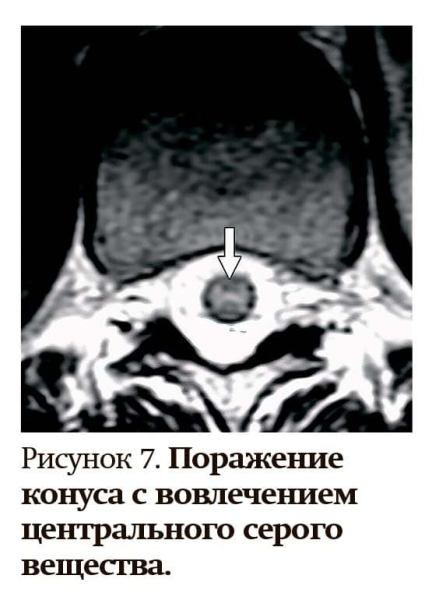

— При остром миелите как проявлении ЗСОНМ чаще встречается поперечно-распространенный миелит с поражением более 50 % площади поперечного сечения, центрально и сзади, — уточнила Татьяна Чернуха. — На МРТ с контрастом видны яркие пятна на Т2-режиме (см. рис. 4).